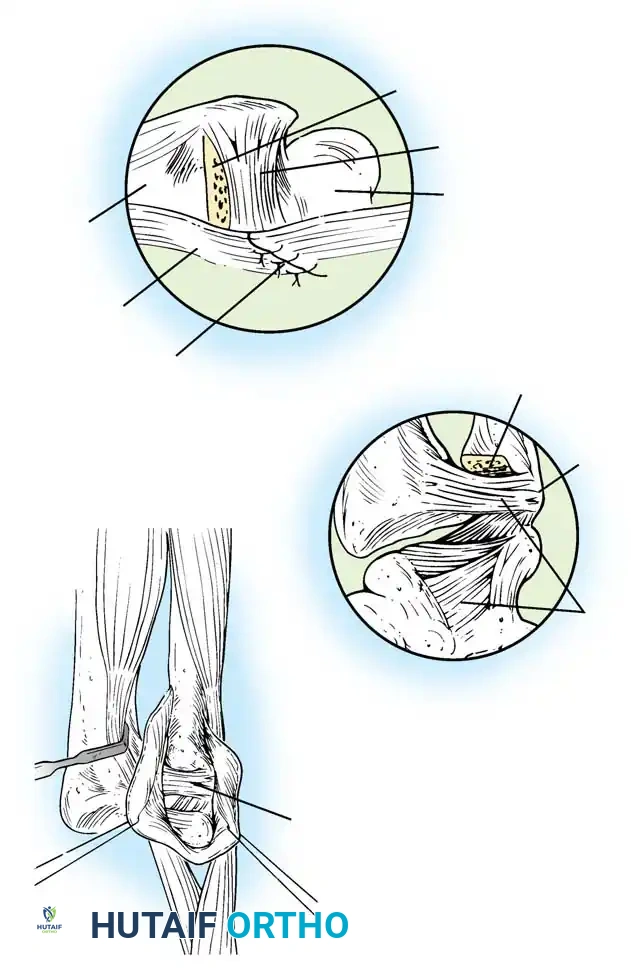

Palmer Classification of TFCC Abnormalities

Palmer revolutionized the understanding of TFCC pathology by categorizing lesions into traumatic (Class 1) and degenerative (Class 2) groups.

Class 1: Traumatic Lesions

These typically result from forced forearm rotation or axial loading, often associated with distal radius fractures.

* 1A: Central perforation of the articular disc (avascular zone).

* 1B: Ulnar avulsion (with or without ulnar styloid fracture). Involves the highly vascularized periphery.

* 1C: Distal avulsion (involving ulnocarpal ligaments), leading to volar ulnar carpal "sag."

* 1D: Radial avulsion (with or without sigmoid notch fracture).

Illustration of various TFCC tear patterns and their respective biomechanical implications for DRUJ stability.

Surgical Technique: Repair of Ulnar Avulsions (Class 1B)

Class 1B lesions involve the vascularized peripheral attachment at the ulnar fovea. These lesions are amenable to repair and are a primary cause of DRUJ instability if left untreated.

Arthroscopic and Open Repair Principles:

If the ulnar styloid is fractured at its base, open reduction and internal fixation (ORIF) of the styloid often restores TFCC tension. If the styloid is intact but the foveal attachment is avulsed, an arthroscopic or open transosseous repair is indicated.

Preparation of the distal ulna: Drill holes are created at the fovea to facilitate transosseous suture passage for anatomic TFCC reattachment.